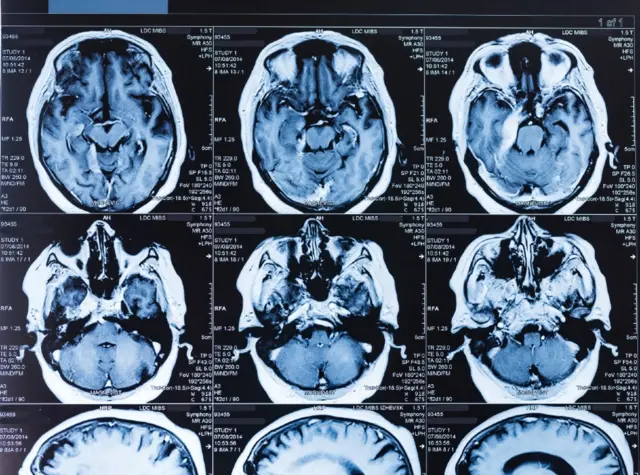

Fuente de la imagen, Science Photo Library

"El estrés sostenido puede producir muerte en el hipocampo, una estructura fundamental de la memoria, y puede producir problemas de memoria y de concentración", dice el profesor.

Fuente de la imagen, Getty Images

De acuerdo con esa organización, varios estudios han mostrado diferencias en la función del hipocampo en niños cuyo cuidado se ha descuidado o que han sufrido abuso.

"Hay una disminución de la activación del hipocampo cuando se recuperan recuerdos de la autobiografía positiva", así como también durante el aprendizaje asociativo, "cuando los niños aprenden y recuerdan nuevas relaciones entre elementos que no están conectados".